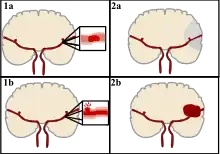

Strokes can be classified into two major categories: ischemic and hemorrhagic.[18] Ischemic strokes are caused by interruption of the blood supply to the brain, while hemorrhagic strokes result from the rupture of a blood vessel or an abnormal vascular structure. About 87% of strokes are ischemic, the rest being hemorrhagic. Bleeding can develop inside areas of ischemia, a condition known as "hemorrhagic transformation." It is unknown how many hemorrhagic strokes actually start as ischemic strokes.[2]

There are two main types of hemorrhagic stroke:[28][29]

- Intracerebral hemorrhage, which is basically bleeding within the brain itself (when an artery in the brain bursts, flooding the surrounding tissue with blood), due to either intraparenchymal hemorrhage (bleeding within the brain tissue) or intraventricular hemorrhage (bleeding within the brain's ventricular system).

- Subarachnoid hemorrhage, which is basically bleeding that occurs outside of the brain tissue but still within the skull, and precisely between the arachnoid mater and pia mater (the delicate innermost layer of the three layers of the meninges that surround the brain).